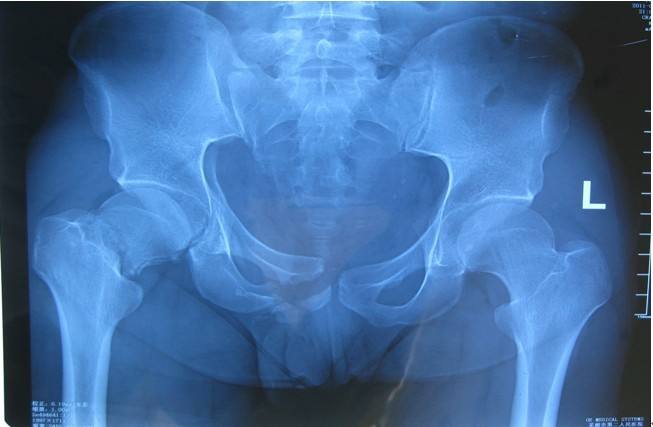

髋骨由髂骨、坐骨和耻骨三部分组成,其外侧面有一个大而深的窝称为髋臼,与股骨头组成髋关节。髋臼是髋关节的重要组成部分,由于髋关节负重大,活动度大,因此很容易发生损伤。

髋臼骨折早期主要表现为髋关节局部疼痛及活动受限,如并发股骨头脱位则表现为相应的下肢畸形与弹性固定。当发生髋关节中心性脱位时,其疼痛及功能障碍程度均不如髋关节前、后脱位,体征也不明显,脱位严重者可表现为患肢缩短。髋臼骨折时可能并发有盆腔内大出血、尿道或神经损伤,以及骨盆环的断裂和同侧下肢骨折。》髋臼骨折要怎么办?如何治疗?